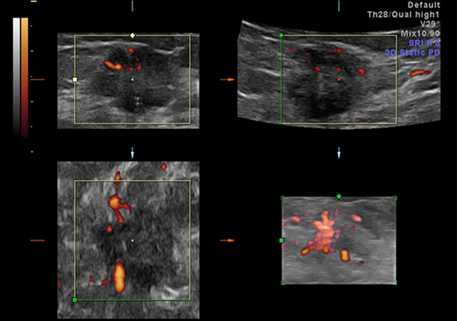

На рисунке опухоль молочной железы показана в режиме трехмерного энергетического допплеровского картирования до и после введения контрастного вещества. На усиленном 3D-изображении четко видна разветвленная внутриопухолевая сосудистая сеть (в двух плоскостях) и намного более крупные периферийные питающие сосуды. Это может означать, что для демонстрации хаотичной извилистости сосудов, связанных с неоваскуляризацией опухоли, 3D-режим подходит больше, чем 2D-режим.